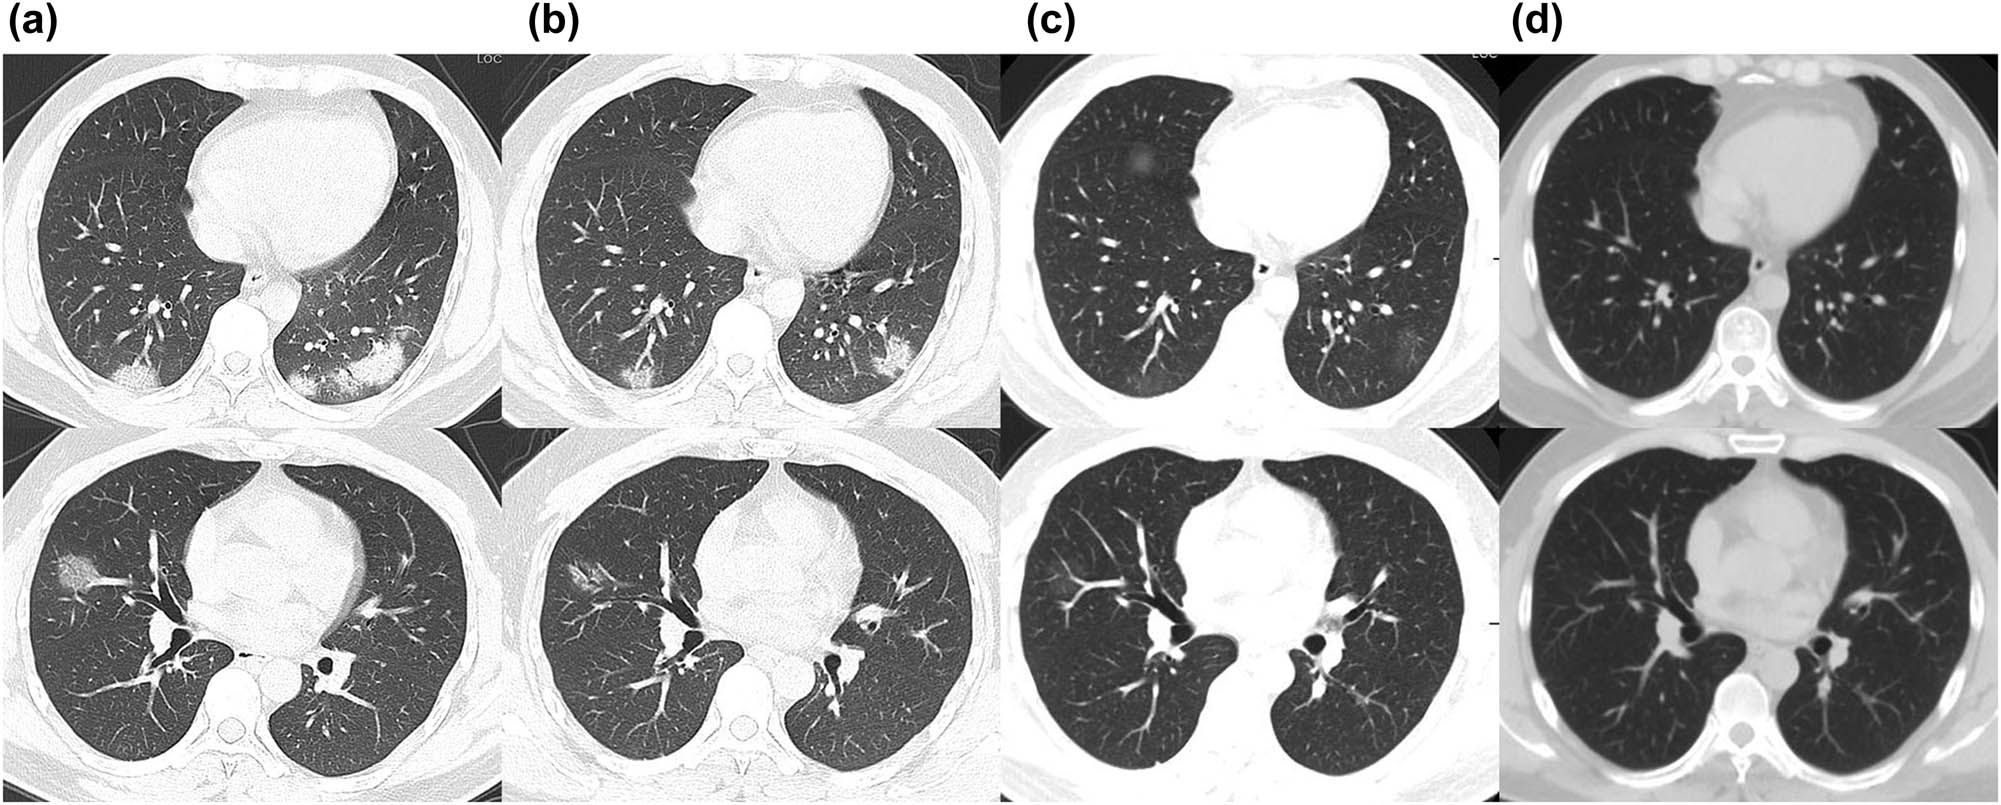

No specific signs were observed on physical examination. However, the oropharyngeal swabs were SARS-CoV-2 PCR-positive, as assessed by Hefei city center for disease control and prevention (CDC) on February 4, 2020 and confirmed by Anhui provincial CDC on the following day. The chest CT on February 6 showed multiple nodular and patchy high-density shadows in the bilateral lung areas (Figure 1a).

Chest CT images of the patient. (a) Multiple nodular and patchy high-density shadows on February 6; (b) Partial absorption of multiple nodular and patchy high-density shadows with ground-glass opacity on February 13; (c) Most absorbed with few parts of ground-glass opacity on March 5; (d) Normal CT image on April 29.

The patient was treated with lopinavir-ritonavir 500 mg po. bid, oxygen inhalation, N-acetylcysteine (NAC) 4.0 ivgtt. qd., and other symptomatic supportive treatment according to the COVID-19 guidelines[2,4]. The symptoms recovered satisfactorily, and the temperature dropped back to normal since day 3. Nonetheless, a chest CT scan on February 13 showed multiple nodular and patchy high-density shadows and ground-glass opacity, which was partially absorbed (Figure 1b).

When the patient revisited the hepatology outpatient on March 5 after quarantine, the CT scan showed only a few ground-glass opacity, while the ALT level was elevated to 1,029 IU/L, following which he was admitted again to our department for chronic hepatitis B (CHB) (Figure 1c). Subsequently, he underwent the SARS-CoV-2 PCR screening that was reported positive on March 7. Thus, he was sent to the quarantine department, and the glutathione dose was reduced to 1.8 ivgtt. qd., while magnesium isoglycyrrhizinate 150 mg ivgtt. qd. and polyene phosphatidylcholine 15 mL ivgtt. qd. were administered along with tenofovir 300 mg qd. Daily, SARS-CoV-2 virus PCR test was performed from March 9–12 with negative results. He was then discharged on March 13 for the second time, while his ALT level was dropped back to 342 IU/L. Oral diammonium glycyrrhizinate and tenofovir were also given, and the ALT returned to the normal level on April 1.

During the months of March, April, and May, his SARS-CoV-2 virus PCR test was lingering between positive and negative, and the patient was isolated either at the quarantine outpost or at home. Chinese CDC was confused about his COVID-19 test result, and hence, he was sent to our fever outpatient on April 29 to validate the test results. Chest CT and SARS-CoV-2 PCR did not show any specific abnormality (Figure 1d). On June 3, the patient was assessed at the local hospital. With supportive treatment, the virus PCR test was negative three times on June 4, 5, and 6, respectively, following which, he was discharged on June 8. As of June 15, the patient was still under observation at home anxiously awaiting future test results (Figure 2).